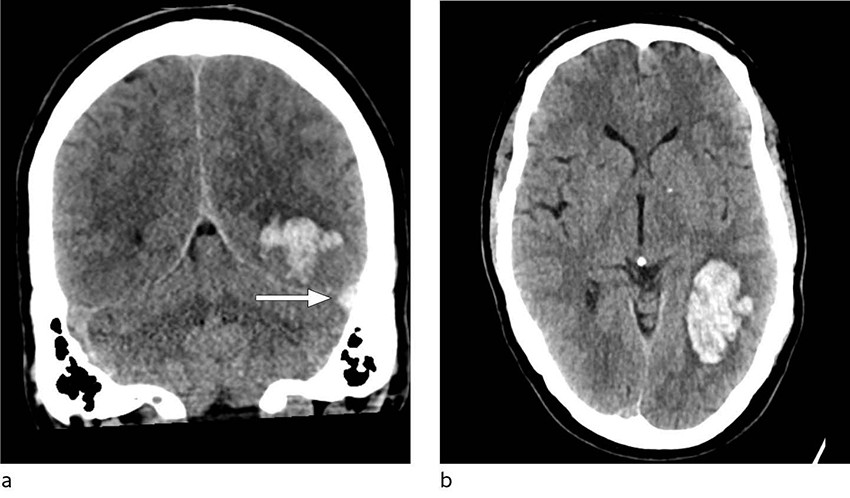

Ved innkomst fremsto han forvirret, søvnig og med afasi. CT caput avdekket intracerebral blødning i venstre temporallapp, og pasienten ble overflyttet til universitetssykehus for observasjon. Ved ankomst der var pasienten våken, men desorientert og hadde afasi uten andre fokalnevrologiske utfall. Han skåret 4 poeng på National Institutes of Health Stroke Scale, forenlig med et mindre hjerneslag. Kontroll-CT caput uten kontrast viste uendret størrelse av hjerneblødningen, og det ble reist mistanke om hemoragisk venøst infarkt grunnet tegn til cerebral venetrombose (figur 1). Supplerende CT-venografi viste manglende kontrastfylning av sinus transversus og sinus sigmoideus på venstre side, som bekreftet diagnosen (figur 2). Det ble samme dag startet behandling med lavmolekylært heparin i form av dalteparin 100 IE/kg to ganger daglig.